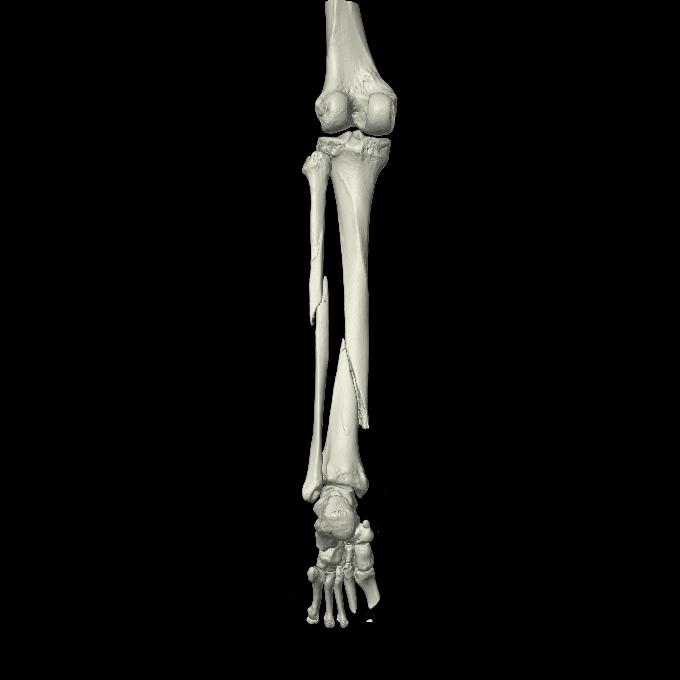

102803 1/12(キウスなし) 1/27 左下腿 4R 30歳女性 左脛骨軸内釘